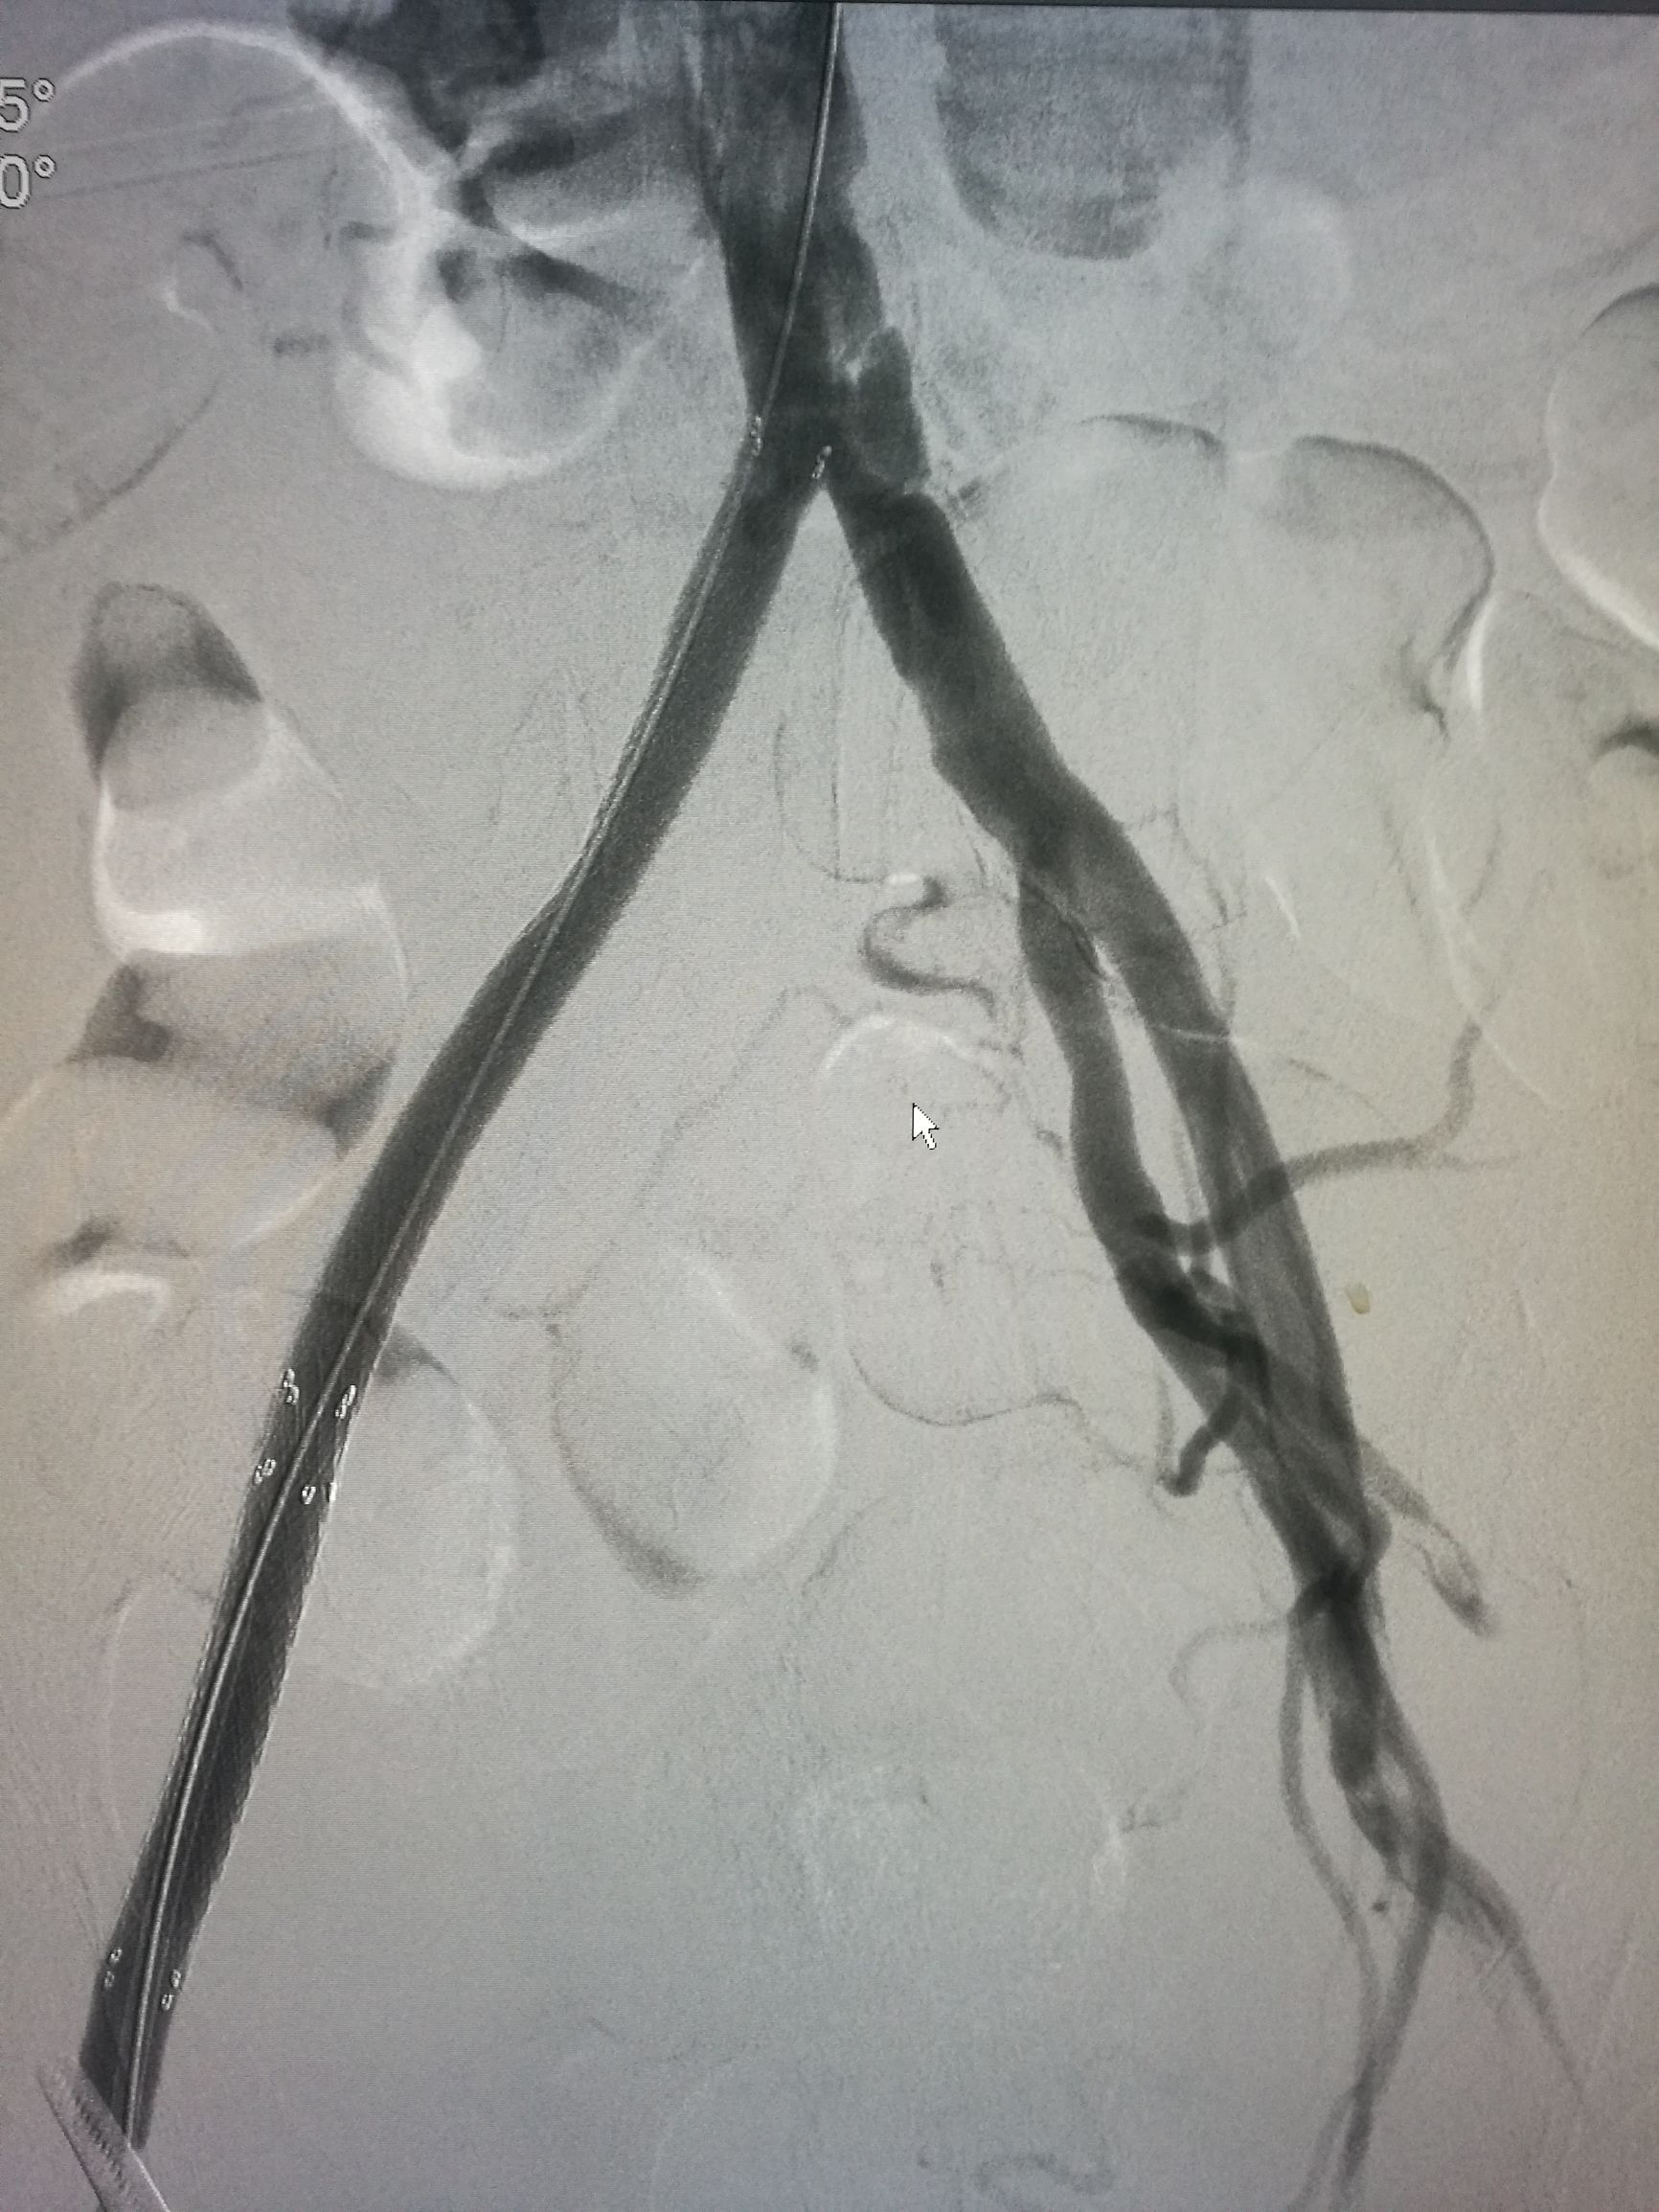

患者平卧位,常规消毒铺单,局麻下切开显露右侧股总动脉和股深动脉、股浅动脉。全身肝素化后,切开股动脉,对股浅动脉取栓后远侧回血好,对股深动脉反复取栓后出现汹涌回血。近端取栓后用导丝导管通过闭塞段到达腹主动脉下段,造影证实在真腔,用5*80mm球囊扩张后造影,髂动脉内有部分充盈缺损。植入巴德Fluency8*100和8*60覆膜支架后用7*60球囊扩张,造影管腔光滑(如图)。缝合动脉切口,关闭伤口,术毕。